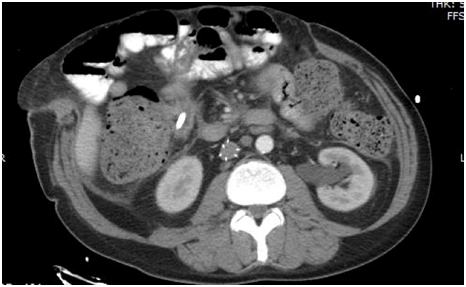

Three main factors were involved in the success of this case. In regards to smoking cessation, the patient started on a nicotine patch while in the hospital before discharge and was able to be completely free from nicotine 2months before the procedure. Preoperatively, it was stressed to the patient that the reconstruction would not proceed unless nicotine cessation was performed. Secondly, a weight loss protocol was undertaken. Preoperatively, the patient was given a goal to lose 40 pounds before surgery. His starting weight 4months prior to his reconstruction was 227 pounds. His weight loss program was coordinated with a certified dietician in our practice. Meal management and exercise logs were created for the patient to account for his weight loss. His final weight was 211 pounds before surgery which was deemed acceptable for reconstruction; however, it did not meet the 40 pound goal. Nutritional markers were not used as a marker of correction for his nutritional status. Finally, tissue expander process was initiated after PMT tissue expanders were inserted into each flank six months prior to reconstruction. Tissue expansion occurred over 16weeks. An overall volume of 1325ml was instilled into the expanders with the patient undergoing fill sessions of 100ml per session. A preoperative CT scan was performed to demonstrate the abdominal wall defect (Figure 1).

Figure 1 Preoperative CT scan demonstrating abdominal wall defect.